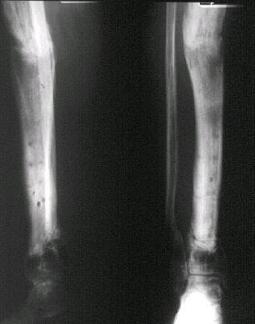

[Ortho] Открытый перелом голени, некроз кожного лоскута

Имя     : #7.jpg

Тип     : image/jpeg

Размер  : 20264 байтов

Url     : http://weborto.net:8080/pipermail/ortho/attachments/20080506/962ee10e/attachment-0005.jpg